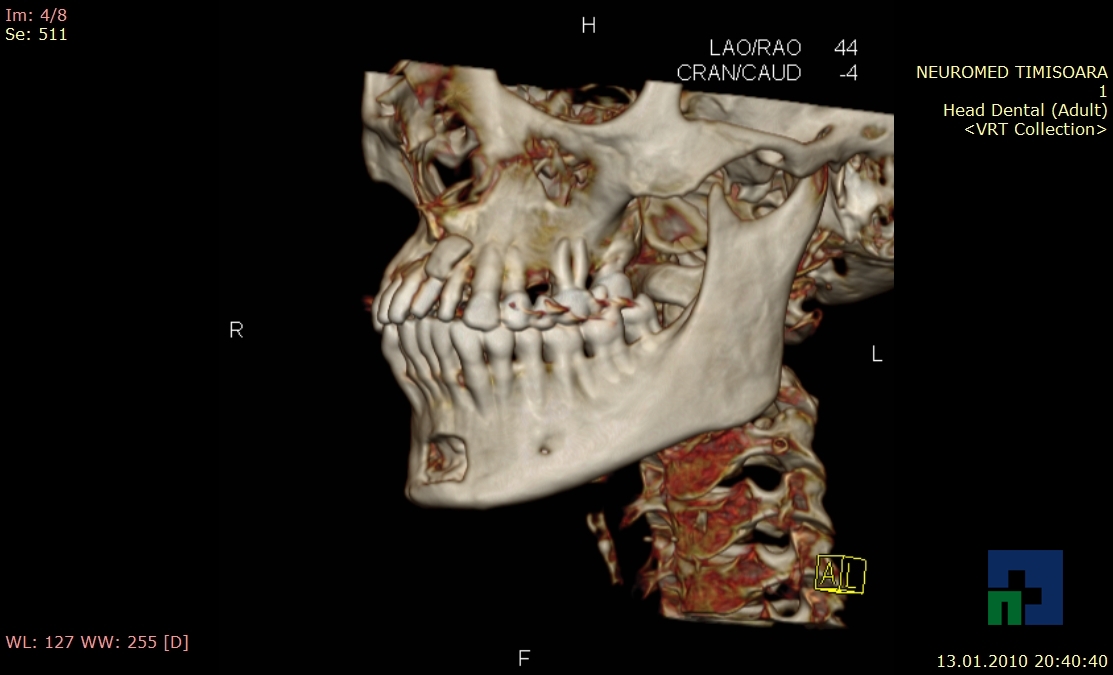

- Diagnosticul fracturilor:

- Unice

- Multiple

- Cu înfundare

- Complexe cranio-sinusale

- Complexe cranio-etmoidale

- Complexe cranio-orbitare

- Complexe cranio-faciale